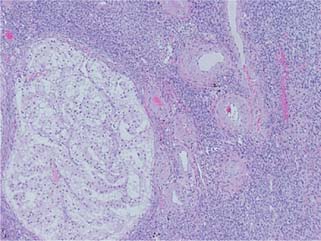

Microscopic examination revealed a tumor composed of nests of clear cells surrounded by interconnecting vascular framework. Cells with eosinophilic cytoplasm were also noted in combination with the clear cells. Immunohistochemical stains, including vimentin, were positive, and CD10 showed diffuse membranous positivity. Eosinophilic nucleoli were identifiable at 100×, consistent with Grade 3 tumor using the International Society of Urological Pathology (ISUP)/WHO grading scheme (13). No sarcomatoid or rhabdoid areas were noted. These findings rendered a diagnosis of left kidney clear cell RCC, which extended into the renal vein, left ovarian vein and uterus, left fallopian tube, and bilateral ovaries (Figure 4). The final pathologic stage was pT4N1M1.

Figure 4: Microscopic evaluation of the tumor revealed nests of clear cells surrounded by interconnecting vascular framework, consistent with the ultimate diagnosis of clear cell renal cell carcinoma.